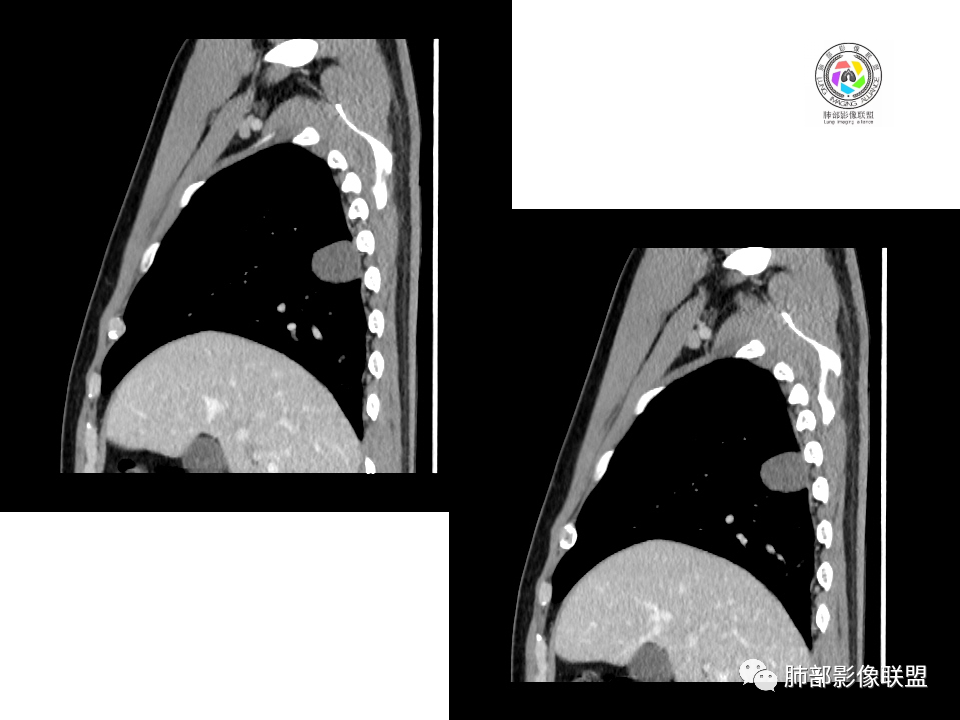

2.右肺下叶背段胸膜下块影,边界清楚光整,上下极见磨玻璃晕,未见明显分叶毛刺和棘状突起,未见胸膜凹陷或胸壁侵入。密度均匀,轻度不均匀强化。未见支气管进入。

显然本例焦点在于背段那个边缘光整的块影!

1.边缘光整干净,大病灶缺乏坏死等,不符合鳞癌影像学特征。尽管有吸烟史,还是偏年轻。

4.良性占位绕不过去,如发生于该部位的孤立性纤维瘤等……

病灶不均匀强化可以将含液支气管囊肿排除在外。